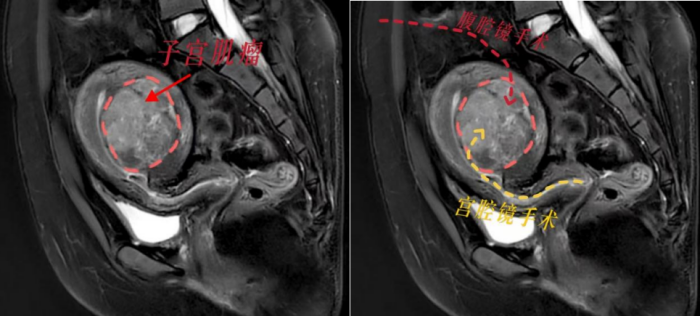

妇产科三区副主任魏馨分析,宫腔镜手术无需腹部切口,通过自然腔道进行,切除肌瘤无需切开子宫肌层,能最大程度保护患者生育力。但是根据子宫肌瘤诊治专家共识,像小丽这样的病例并不适合宫腔镜手术,因为手术风险极高,难以一次性切除干净,还可能引发水中毒、子宫内膜损伤等严重并发症。而如果选择腹腔镜下子宫肌瘤剥除术,就必须把子宫肌层完全切开,术后至少需要等待1年才能怀孕,且怀孕后子宫破裂的风险极大。这对于渴望成为母亲的小丽来说,无疑是沉重的打击。

面对患者强烈的生育需求,魏馨主任带领团队迎难而上,决心挑战“不可能”!经过反复研究病情和推敲手术方案,魏馨主任凭借丰富的临床经验和精湛的宫腔镜手术技巧,成功为小丽实施了高难度宫腔镜下子宫肌瘤切除手术。手术不仅一次性将肌瘤彻底切除,而且没有损伤子宫肌层和内膜,术中出血少,术后恢复快,未出现任何并发症。术后第2天,小丽便顺利出院,术后3个月即可备孕,重燃了她成为母亲的希望。